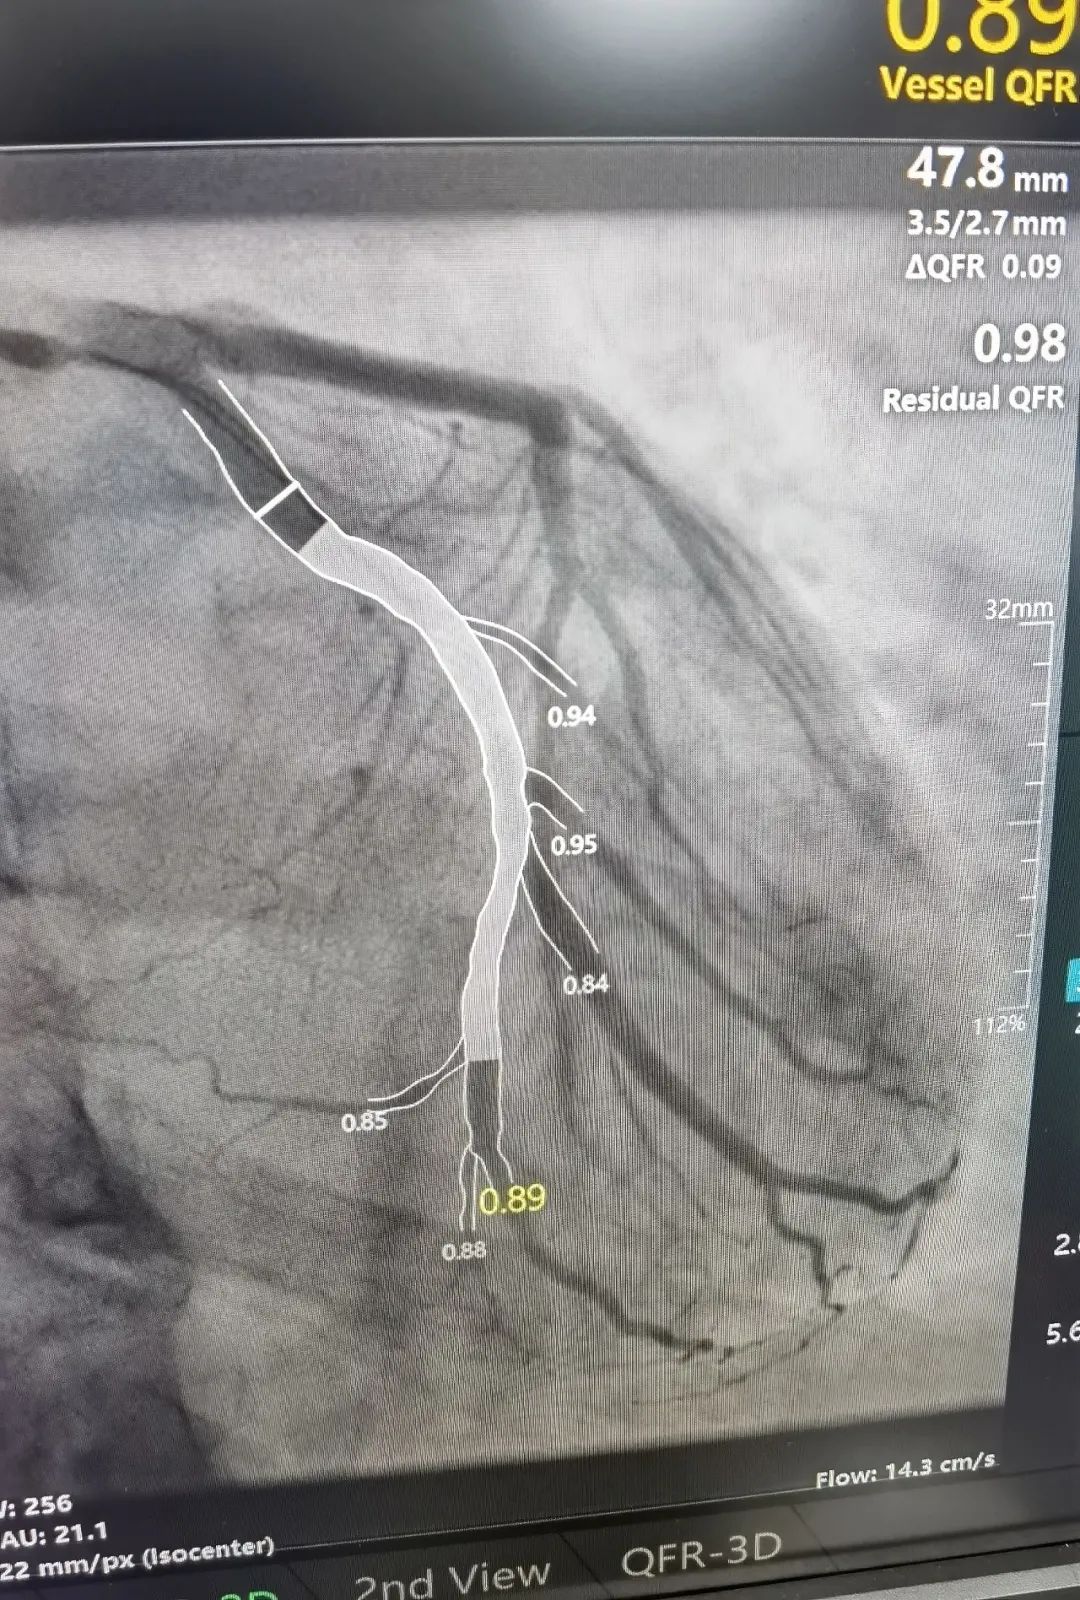

术中的 QFR 依靠冠脉造影三维重建技术和血液动力学系统,并融入人工智能血流定量;精确分析狭窄冠脉血管的功能学指标,是无创、精确评估冠脉生理功能指标的「新标准」。

这位患者在 QFR 指导下对于分叉病变使用药物球囊治疗,避免了支架的植入对分叉另外一根血管的压迫,从术前和术后的 QFR 数值来看,手术收到了非常好的疗效。同时该患者不需要长期服用双联抗血小板药物,只需服用双联抗血小板药物一到三个月,因此对于特定病变和特定人群具有不少优势。

术后影像

术后影像学效果和血流恢复情况都非常满意,此项手术的成功开展也是继 8 月 21 日成功实施经皮主动脉瓣置换(TAVI)后的又一例嘉湖地区首例。